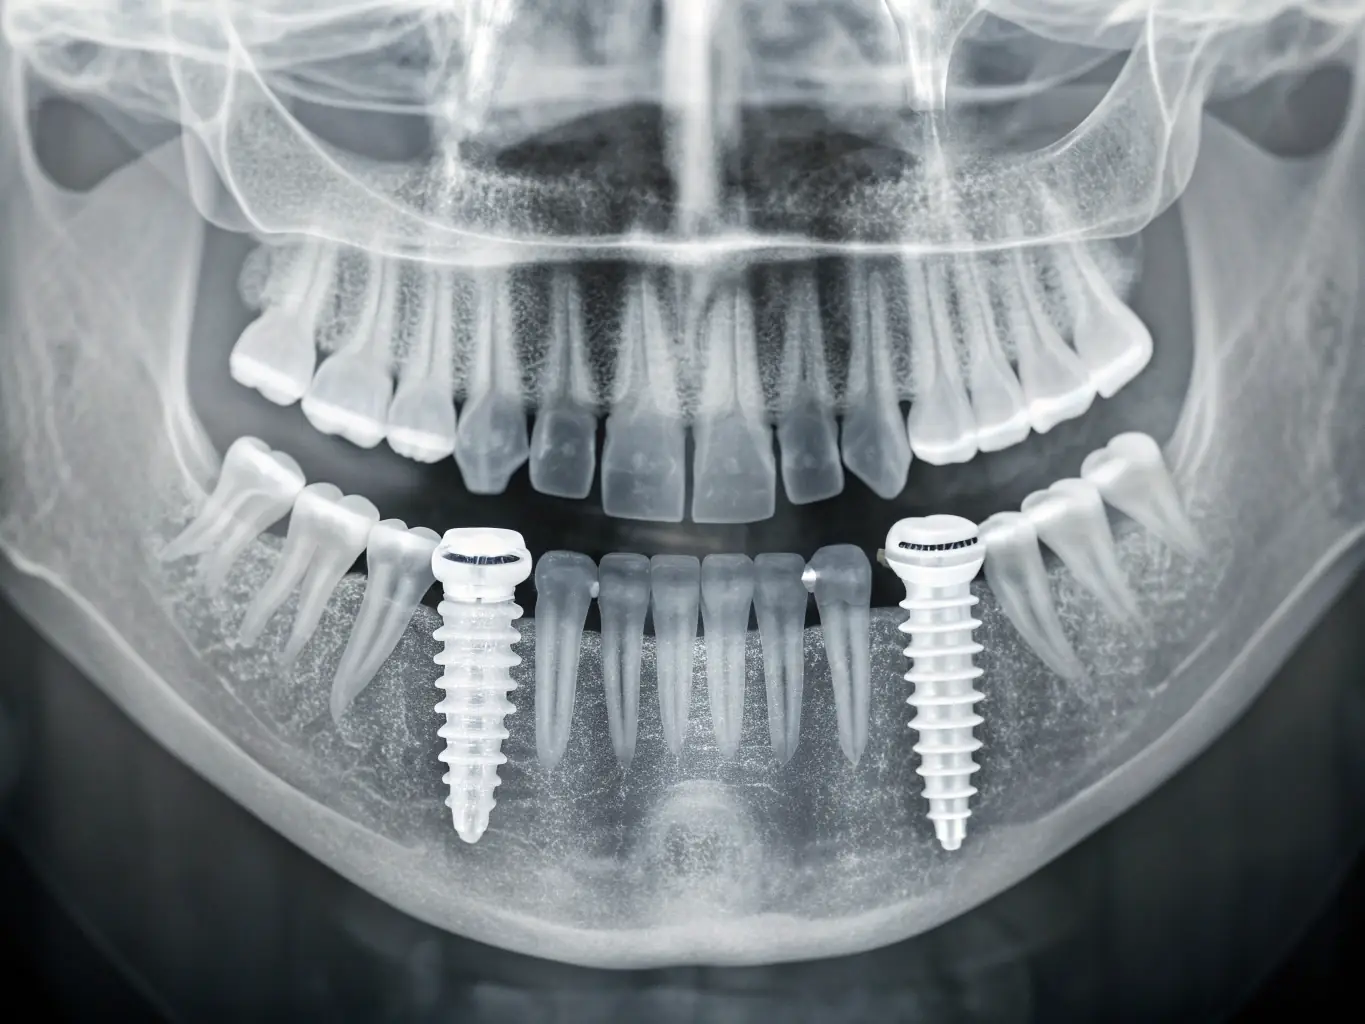

Digital X-Ray is an advanced dental imaging technology that helps detect problems early, even before pain or visible symptoms appear. It allows your dentist to see what cannot be seen during a regular dental examination. With quick results and very low radiation, Digital X-Ray plays an important role in accurate diagnosis and successful dental treatment.

- Clear and Detailed ImagesHigh-resolution images allow accurate detection of:

- Cavities between teeth

- Tooth infections and abscesses

- Bone loss and gum disease

- Impacted or missing teeth

- Problems beneath fillings or crowns

- Dental implant assessment